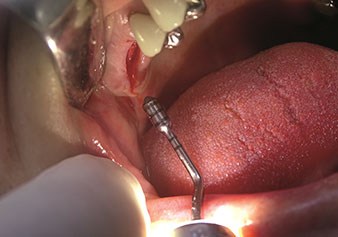

One application, which is often underestimated is the atraumatic extraction of tooth roots or root fragments in the scope of alveolar management. The fine periotomes, which are currently available in two versions (EX1 and EX2 from W&H), can also be used to remove teeth which have previously undergone special endodontic treatment or ankylosed roots with ease. This results in extraction alveoli where both the hard and soft tissue are fully intact as it is generally possible to avoid reflection.

This establishes the optimal basis for subsequent or immediate implant treatment (Figures 1 and 2 included with the kind permission of Dr Torsten Conrad, Bingen a. Rhein).

Fine periotome (EX1 instrument)

Fig. 1: Fine periotome (EX1 instrument).

Photo: © Dr Torsten Conrad (Bingen a. Rhein)